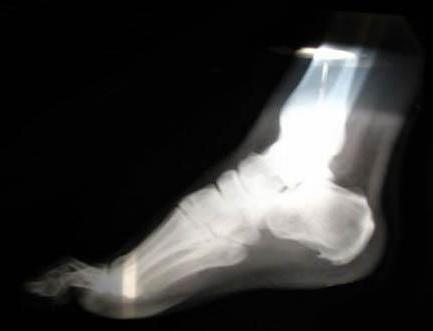

Рентгенодіагностика і рентгенотерапія. Рентгенологічно п'яткові шпори виявляються у вигляді кісткових розростань на підошовної поверхні п'яткової кістки, а також на задній поверхні її горба біля місця прикріплення сухожилля (рис.). Ці розростання зливаються зі склерозированным поверхневим шаром кістки. Форма їх різна: шиповидна, клювовидная, а іноді у вигляді плоского шорсткого наросту, прилеглого до поверхні кістки своїм широким підставою. Клінічні прояви, зумовлені змінами в оточуючих шпору м'яких тканинах (бурсити, фіброзіти), прямого відображення на рентгенограмах не мають.

Основним симптомом кісткових шпор є болі; при шпорі п'яти хворі набувають своєрідну ходу - наступають тільки на передній відділ стопи і пальці. Діагноз підтверджується рентгенографією - визначається крючковидное кісткове розростання на нижній або задній поверхні п'яткової бугра.

Основну роль в діагностиці кісткових шпор відіграє рентгенологічне обстеження. Диференціювати кісткові шпори доводиться з хронічним артритом і остеомієлітом даній області, а також з подагрою, причому вирішальну роль відіграє рентгенографія.